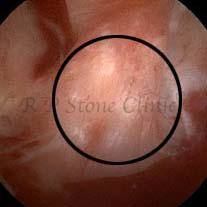

Kidney stone is a solid mass of CRYSTALS. It is the process of crystallization which initiates the formation of kidney stones. This happens in nephrons or units of kidney. Once a small crystal is formed, it can both grow & unite with other crystals leading to the formation of small concretion which eventually forms a stone. Once these large crystals detach from the collecting ducts, the process of stone formation starts in the renal collecting system. A recurrent kidney stone former is advised to know a little bit about something known as Randall’s plaque. Alexander Randall discovered plaques on the renal papillae eight decades back based on examination of 1154 pairs of autopsied Kidneys. He described these renal papillary lesions as cream colored or milk patch areas composed of calcium phosphate & calcium carbonate. These plaques could act as NIDUS for formation of KIDNEY STONE. Calcium Oxalate stone can form on this nidus & then detaches from this plaque to become a free floating stone in the collecting system of kidney

These images are taken as snap shots from the video recording of RIRS Surgery done at our hospital. These are Randall’s Plaques seen with Digital FLEX XC & Digital FLEX XC S. The cream or whitish patches are seen on the tips of RENAL PAPILLAE as seen in images below.

Randall’s Plaques may lead to the formation of Stones.

Those kidney stone patients who have Randall’s Plaques in their kidneys are more likely to form stones again (Recurrent Stones).

Stone Patients in whom Randall’s Plaques are detected at the time of RIRS Surgery should undergo regular ultrasound examination for early detection of stones.

Patients of Stones with Randall’s Plaques in their Kidneys should drink plenty of fluids in addition to Orange Juice & Lemonade.